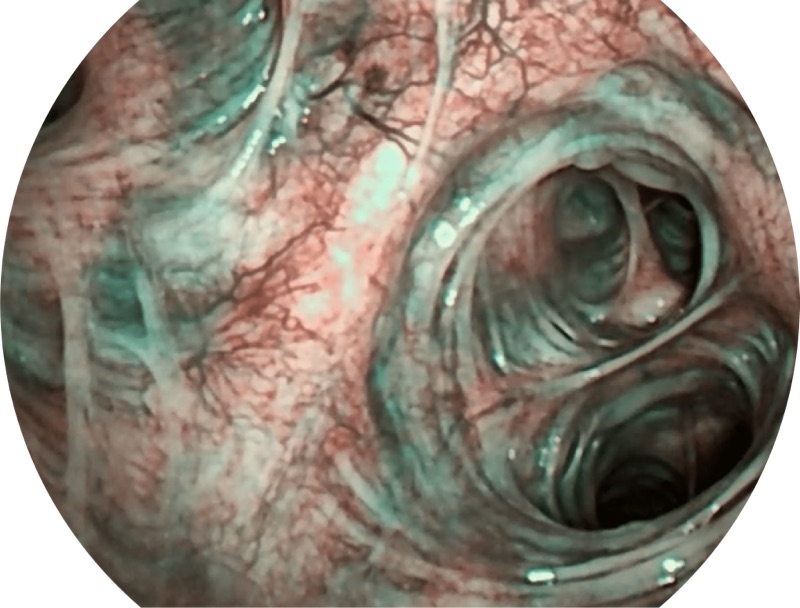

SFI